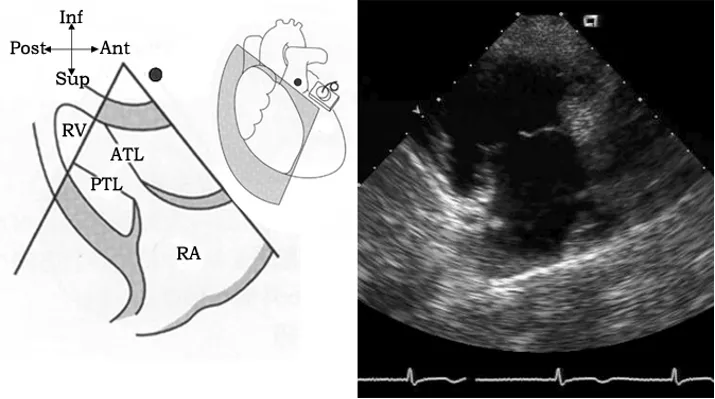

胸骨旁右心室流入道切面

探头位置:探头置于胸骨左缘3、4肋间,在左心室长轴切面基础上顺钟向调整探头15°—30°。

观察内容:右房、右室、三尖瓣前叶、后叶。